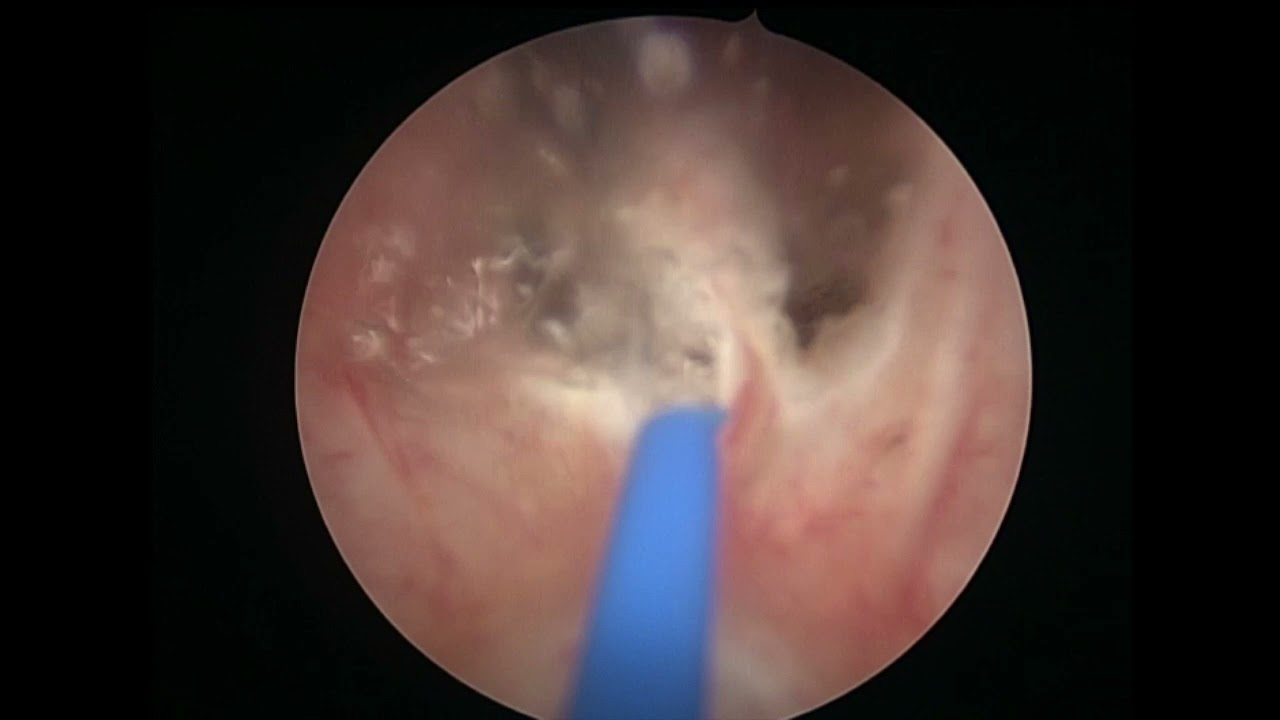

Mi nombre es Miguel Ángel Rodríguez Cabello. Soy médico licenciado por la Universidad de Alcalá y especialista en Urología formado en el Hospital Universitario Ramón y Cajal. Terminé mi formación como especialista en Urología en el año 2015 de la mano de grandes profesionales y maestros, y trato de transmitir todos mi conocimientos y habilidades para el beneficio de mis pacientes. También he completado mi etapa universitaria con el Doctorado, que defendí en la Universidad Autónoma de Madrid en junio de 2023 con resultado Cum Laude. He recibido formación en cirugía robótica (INTUITIVE - DaVinci Xi y SP) en Saint Augustin Clinic de (Burdeos) y estoy acreditado para su utilización por la agencia IRCAD (Strasbourg, France) desde 2017. Tengo amplia experiencia en el manejo de la hiperplasia de próstata con técnicas como la enucleación y vaporización con láser y con la moderna técnica robótica denominada hidroablación - AQUABEAM -, Por último, mi campo de trabajo e investigación más puntera es el diagnóstico y tratamiento del cáncer de próstata (biopsia fusión, terapia focal, prostatectomía radical...), temática que abarca gran parte de mi actividad profesional.

Diagnóstico y tratamiento de la hiperplasia de próstata (HBP) mediante láser, REZÜM y AQUABEAM.

Biopsia de próstata por fusión. Cirugía robótica (DaVinci, AQUABEAM). Cirugía de la hiperplasia de próstata con láser, REZÜM y Aquabeam. Terapia focal en cáncer de próstata (crioterapia, HIFU). Vasectomía sin bisturí. Circuncisión sin bisturí (CIRCURER). Segundas opiniones médicas. Ensayos clínicos en infecciones del tracto urinario.

Siguiendo sus consejos me sometí primero a una operación para extraer dichas piedras y al mes me realice la operación para la hiperplasia mediante la técnica AQUABEAM.

El sistema AQUABEAM, comparando con otros amigos que pasaron por la técnica del laser, me han permitido un postoperatorio cómodo e indoloro.